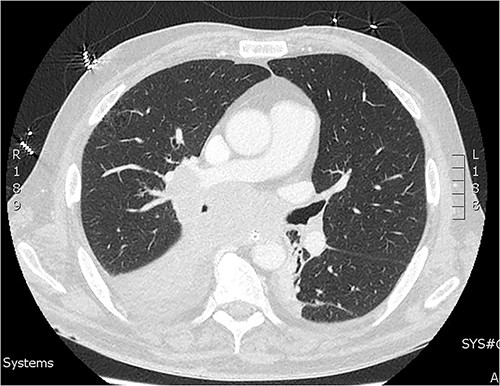

A 60-year-old male presented with 4-h history of acute right lower abdominal pain. He had a history of emphysema, hypertension, heavy cigarette smoking and prostate cancer in remission. On presentation, he was septic with tachycardia (110/min), hypotensive with systolic blood pressure of 90 mmhg and febrile (38.5°C). Abdominal examination revealed peritonism in the right lower quadrant. Computed tomography (CT) scan was performed demonstrating a perforated appendix with a 51 × 31 × 26 mm collection and surrounding fat stranding. CT scan also demonstrated innumerable hepatic nodules, mural thickening of the caecum and sigmoid colon as well as marked mesenteric, para-aortic, portocaval lymphadenopathy and pulmonary consolidation/collapse in the right lower lobe (Fig. 1). Patient underwent an exploratory laparotomy. Intra-operative findings were of a perforated appendix with four quadrant purulent contamination and a thickened and woody sigmoid colon. A subtotal colectomy with end ileostomy was performed. Post operatively the patient remained intubated and ventilated.

On day two of post laparotomy, a CT chest was performed for disease staging (Fig. 2). This study demonstrated a bulky multi-station mediastinal lymphadenopathy contiguous with soft tissue thickening enveloping the right lower lobe and middle lobe bronchi, suggestive of a primary lung cancer. Extubation was attempted on day three post laparotomy, however, the patient desaturated and was re-intubated and ventilated. Following family discussion regarding the poor prognosis care was withdrawn day six and the patient passed away.

CT of the chest from day two admission demonstrating soft tissue mass enveloping the right bronchi.